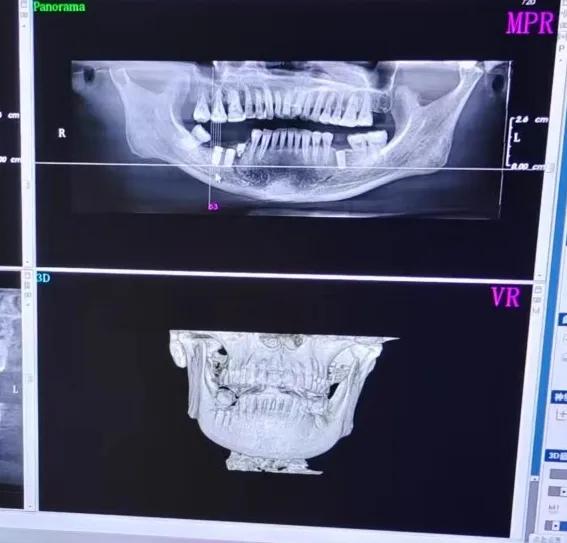

我妈拔牙后种牙记录

我妈牙齿种植后的ct图

最后花费半年时间,我妈重新又拥有了一口能够正常咀嚼进食的牙。应该能陪她到六十五岁,但前提是注意牙齿健康...